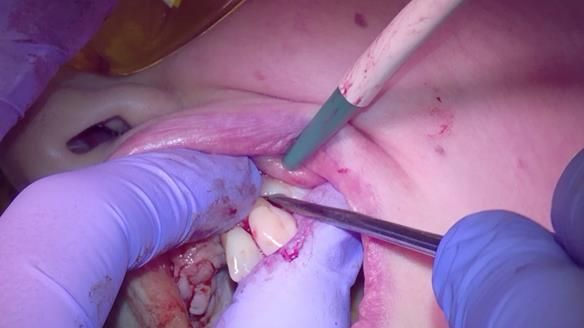

She had previously suffered from generalised periodontitis – stage IV, grade C, currently stable, with reduced attachment across the upper arch.

By the time she came to me, her periodontal condition was stable — but the aesthetics in the upper jaw were very poor.

Dr Syed Abad — my colleague and a Specialist in Periodontics — had successfully stabilised her gum health.

We provided her with an immediate upper denture (Mk 1), followed by a definitive metal-based upper denture (Mk 2). A lower removable partial denture was discussed, to be made only if needed once the upper treatment was complete. However, at review, this wasn’t necessary — Adnana had excellent neuromuscular control and function, even with a shortened dental arch (SDA).